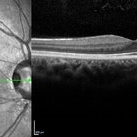

Optic Disc Pit

May 17 2024 by T. P . VIGNESH, MBBS,MS

SD-OCT of the right eye of a 26 year man revealing Optic disc pit .

Photographer: Sivanath

Imaging device: Heidelberg Spectralis

Condition/keywords: Optic disc pit